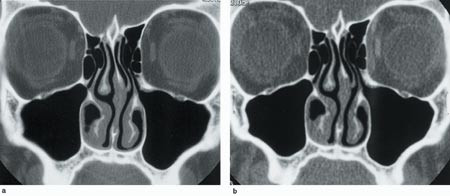

Sensitivitet og spesifisitet for røntgen bihuler og lavdose-CT fremgår av tabell 1. Ved røntgen bihuler var spesifisiteten høy, men sensitiviteten lav (< 50 %) for alle sinusgrupper bortsett fra kjevehulene, hvor sensitiviteten var 80 %. For lavdose-CT var den samlede sensitivitet og spesifisitet for tilstedeværelse eller fravær av sinusitt henholdsvis 95 % og 97 %. Lavdose-CT var ved denne problemstillingen tilnærmet like nøyaktig som standarddose-CT. Den lave mA-verdien med økte artefakter gav få tolkingsproblemer (fig 2).

Vår intensjon var å utvikle en lavdoseprotokoll hvor det var balanse mellom bildekvalitet og stråledose. Generelt vil senkning av mAs-verdien redusere stråledosen, men øke bildestøyen. Redusert snittykkelse og økt snittavstand reduserer også stråledosen. Det er en direkte sammenheng mellom snittykkelse og bildestøy. Ved å utvide bildevinduet blir støyen mindre fremtredende. Vi kom frem til en nedre grense for fremstilling av bihuler ved mAs 40 og snittykkelse 1 mm. Ved lavere verdier dominerte tannfyllingsartefakter og bildestøy. Snittavstanden varierte vi avhengig av de aktuelle anatomiske strukturer, og vi unngikk å bestråle øyets linse direkte. Vi oppnådde med den aktuelle lavdose-CT en reduksjon til under 10 % av standarddosen.